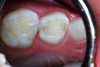

(2.) Lingual and facial maxillary views of 5-year-old patient, 1 year after caries attenuation with SDF. The parents were not concerned about the black staining.

Figure 2

(3.) Lingual and facial maxillary views of 5-year-old patient, 1 year after caries attenuation with SDF. The parents were not concerned about the black staining.

Figure 3